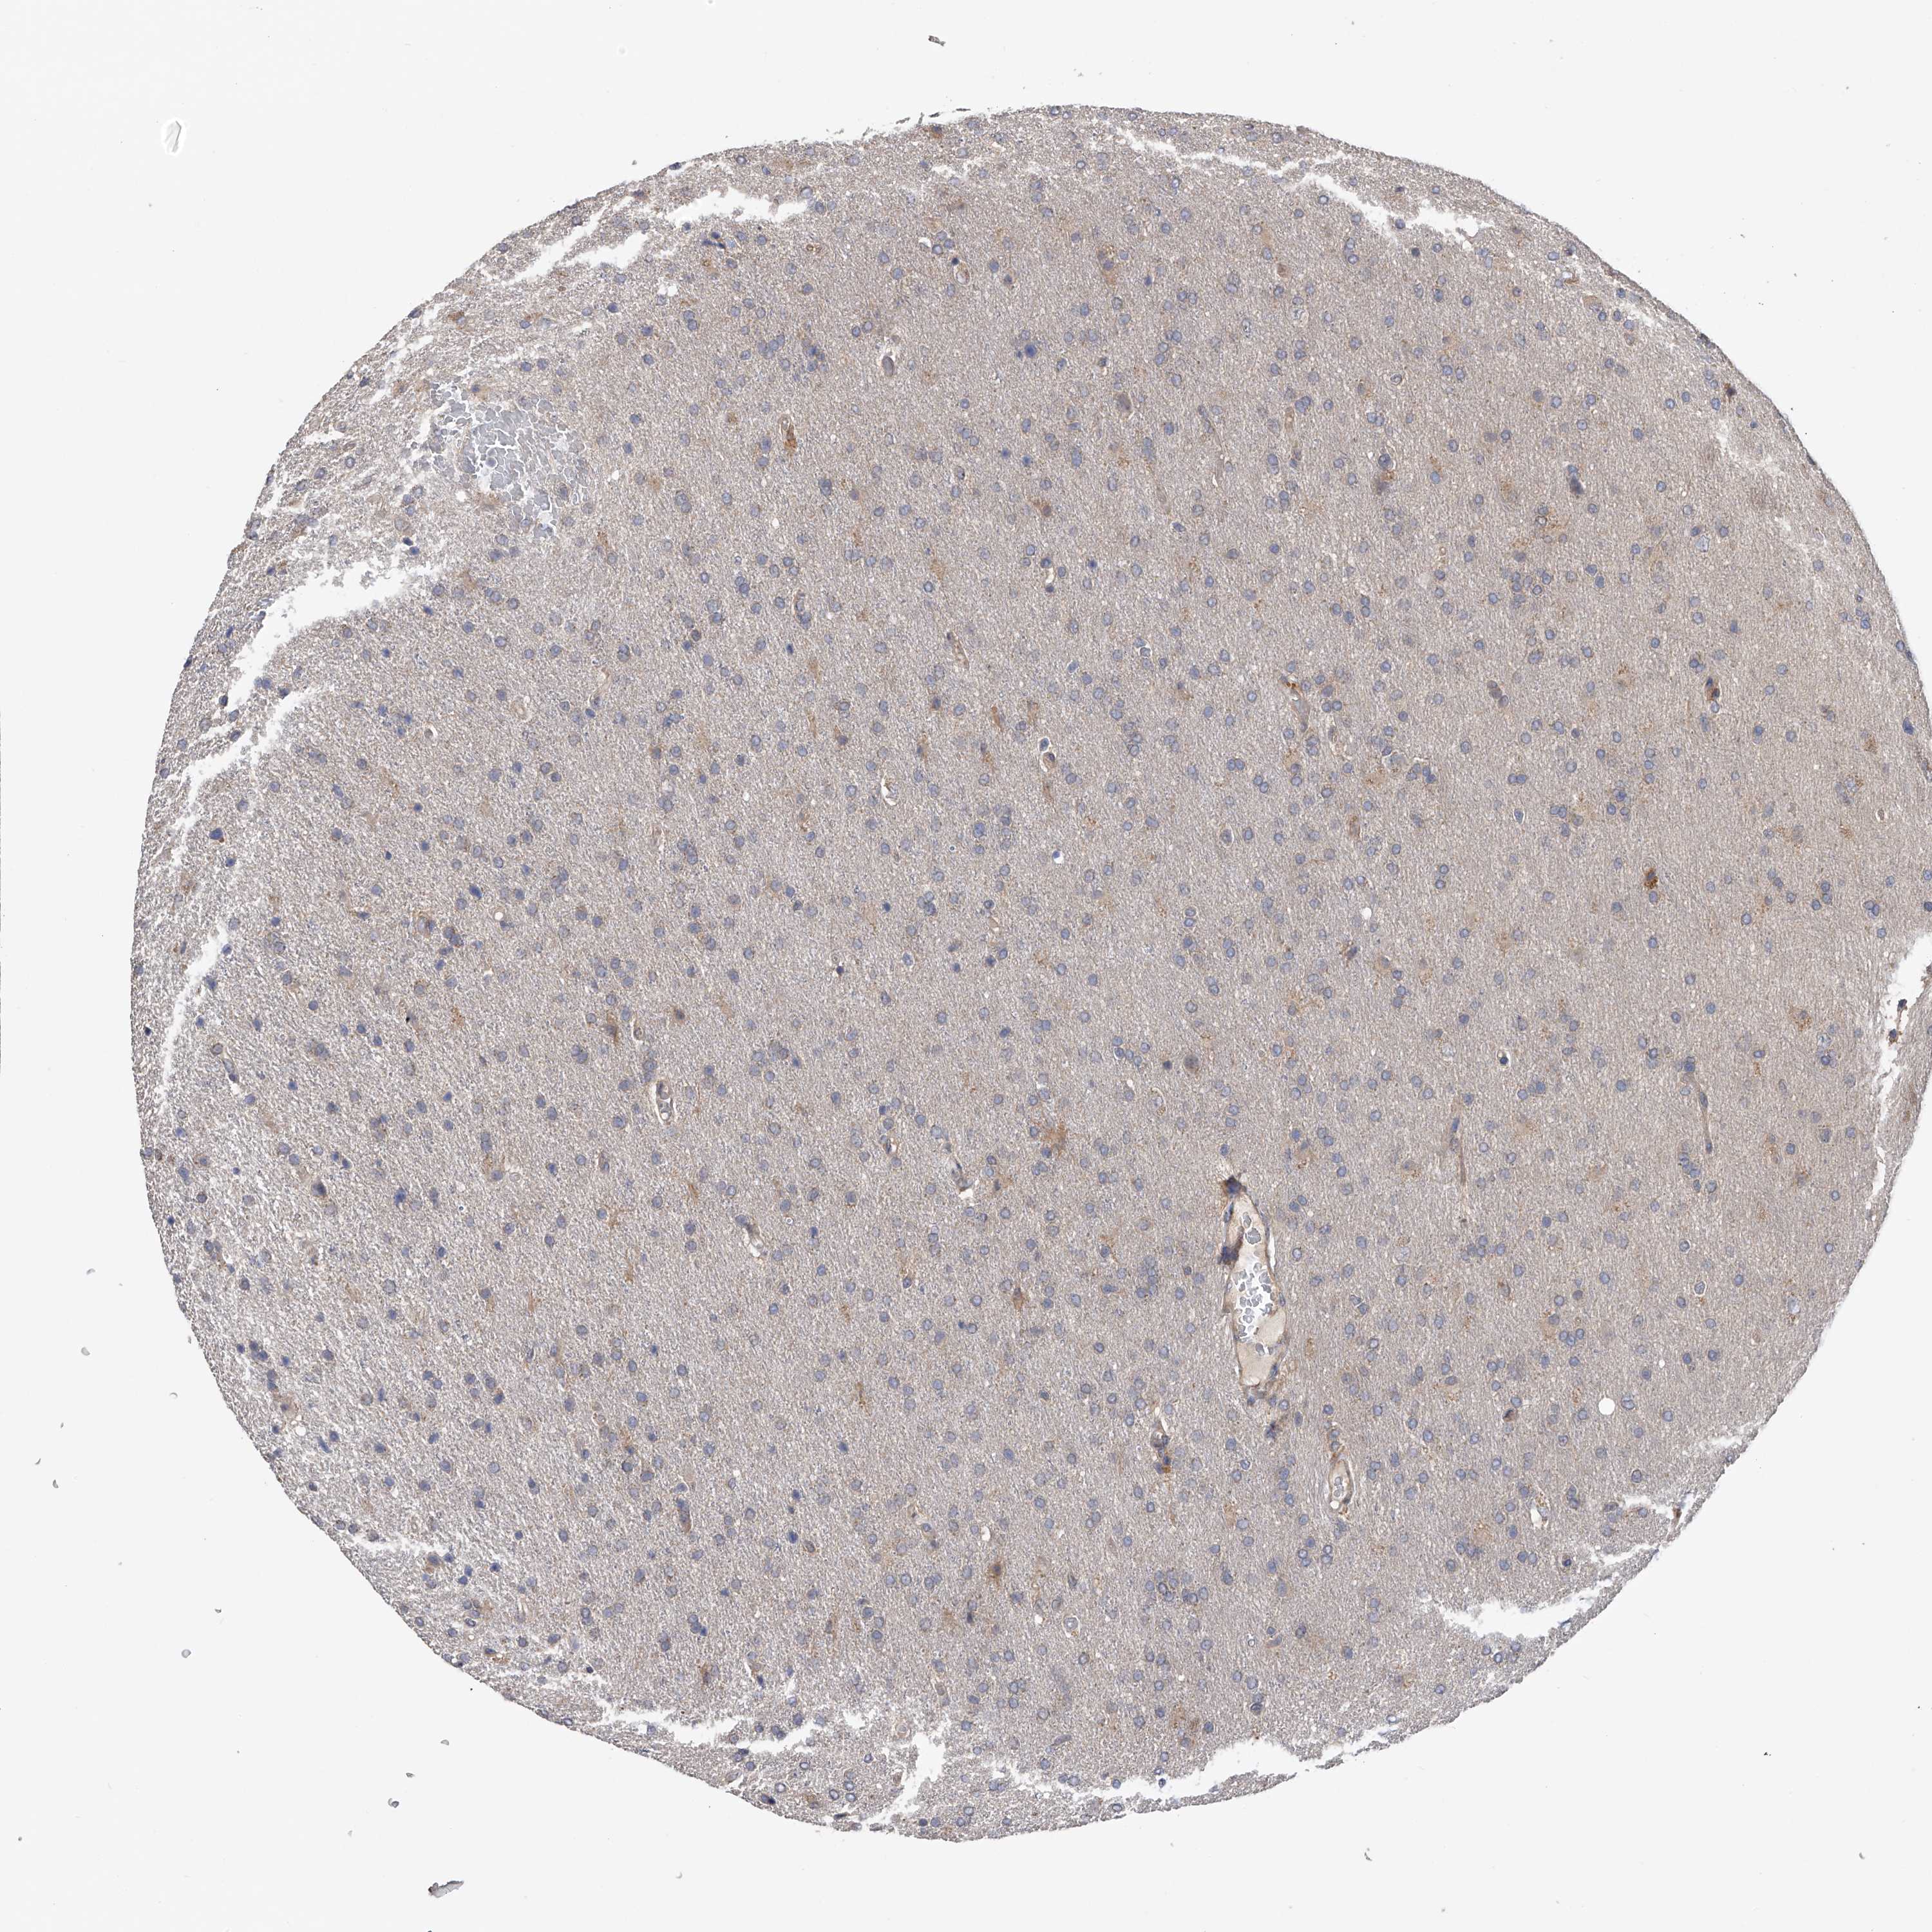

GLIOMA - Protein expressioni

A mouse-over function shows sample information and annotation data. Click on an image to view it in a full screen mode. Samples can be filtered based on level of antibody staining by selecting one or several of the following categories: high, medium, low and not detected. The assay and annotation is described here.

Note that samples used for immunohistochemistry by the Human Protein Atlas do not correspond to samples in the TCGA dataset.

Antibody stainingi

Antibody staining in the annotated cell types in the current human tissue is reported as not detected, low, medium, or high, based on conventional immunohistochemistry profiling in selected tissues. This score is based on the combination of the staining intensity and fraction of stained cells.

Each image is clickable and will lead to virtual microscopy that enables deeper exploration of all samples and also displays staining intensity scores, fraction scores and subcellular localization as well as patient and tissue information for each sample.

Antibody HPA018453

Antibody HPA019055

Antibody HPA028849

Antibody CAB034170

Glioma, malignant, High grade

Glioma, malignant, Low grade

Glioblastoma, NOS